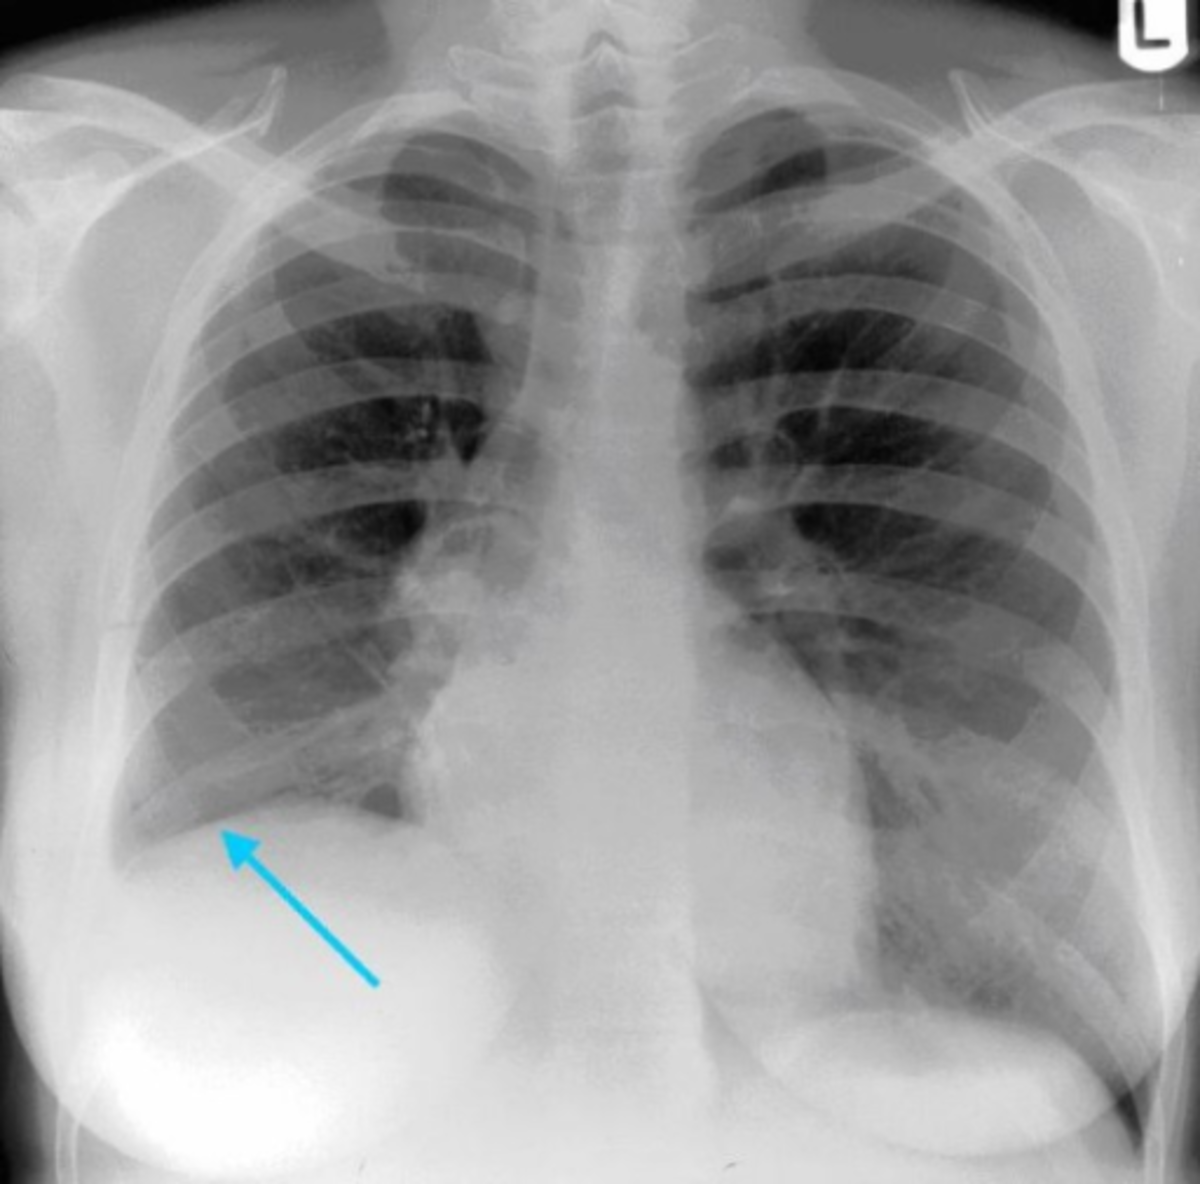

Chest Xray of patient 2 atelectasis in the left lower lung Download Atelectasis Cause Chest X-Ray But other tests may be done to. Atelectasis is a radiopathological sign that can be categorized in many ways. Each approach aims to help identify possible. Occurs as a result of scarring or fibrosis that reduces lung expansion. In most cases affecting adults, atelectasis will appear in the lower left lobe of the lungs. Common etiologies include granulomatous disease, necrotizing. Atelectasis Cause Chest X-Ray.

From www.researchgate.net